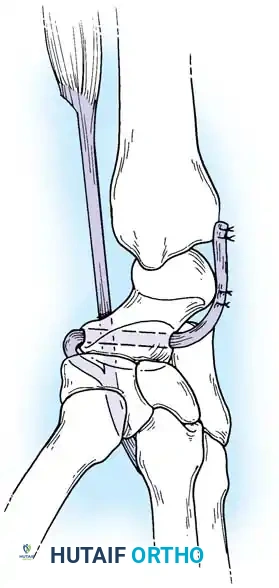

Surgical Approach and Plate Fixation

- Positioning and Incision: The patient is positioned supine with the arm on a hand table. A longitudinal dorsal incision is made centered over Lister’s tubercle, extending distally to the base of the third metacarpal.

- Exposure: The extensor retinaculum is elevated, and the extensor pollicis longus (EPL) is transposed radially. The dorsal capsule is excised to expose the radiocarpal and midcarpal joints.

- Joint Preparation: The dorsal cartilage of the radiocarpal, intercarpal, and third carpometacarpal joints is meticulously denuded down to bleeding subchondral bone.

- Bone Grafting: A local distal radial bone graft portal is utilized. Cancellous bone is harvested from the distal radius metaphysis to augment the fusion sites.

- Plate Application: A 3.5-mm dynamic compression plate (DCP) is applied from distal to proximal. The plate is specifically contoured to provide 10 to 15 degrees of wrist extension. The plate spans the local radial bone graft augmentation, ensuring rigid compression across the fusion mass.

Surgical Warning: Ensure the distal screws engage the dense diaphyseal bone of the third metacarpal without penetrating the palmar cortex, which could tether the flexor tendons. The thickness of the plate distally must be accommodated by adequate soft tissue closure to prevent extensor tendon irritation.